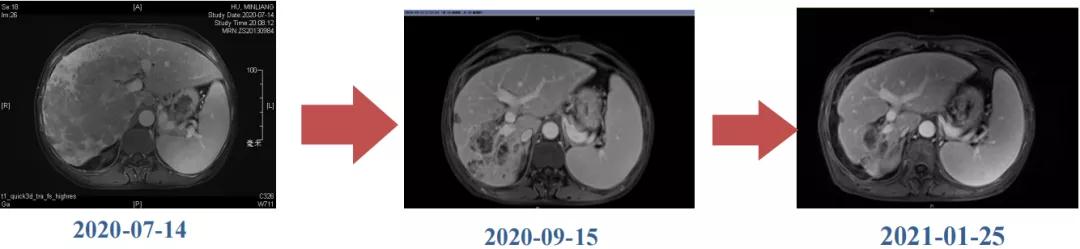

肝脏弹性超声:12kPa。腹部MRI平扫+增强:肝巨块结节性HCC(最大径18.4cm)伴肝内多发转移(最大径3.5cm),肝右静脉广泛癌栓形成;肝硬化伴门脉高压、脾大、少量腹水;肝囊肿;双肺多发转移。胸部CT平扫:两肺多发转移,两肺气肿伴肺大泡,两肺散在慢性炎症,右侧少量胸水。

Δ肝脏MRI,最大肿瘤18.4cm

肿瘤学评估(用药后2个月对比6个月):肝内主瘤明显缩小,动脉期强化降低;子灶消失;门脉右支癌栓明显缩小坏死;肺转移灶缩小,大部分消失。

Δ治疗过程中病灶影像学变化

用药6个月后:肝脏病灶明显缩小,子灶消失,仅有少量动脉期强化;肺转移单个持续缩小稳定,PET CT活性弱;HBV DNA 转阴;可考虑转化切除。